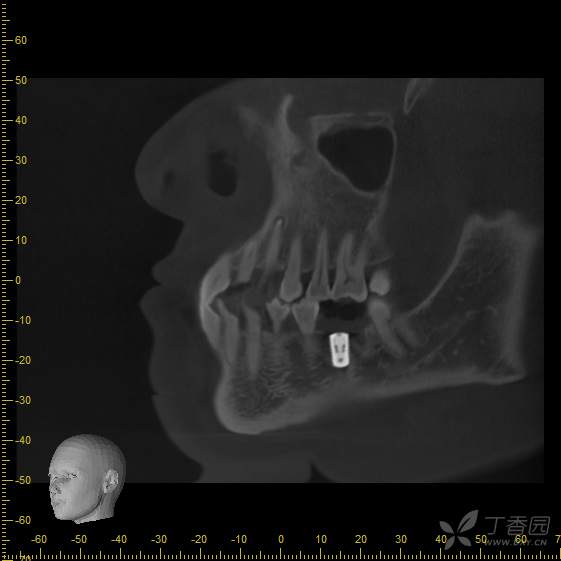

术前cbct,可见36拔牙窝低密度影,牙槽嵴顶骨白线不可见,推理低密度影可能为炎性肉芽组织,矢状位截图,可见牙槽分隔

手术即刻拍摄cbct,手术过程中刮净肉芽组织,碘酊灼烧,大量生理盐水冲洗,植入4.8*8mm骨水平种植体一枚